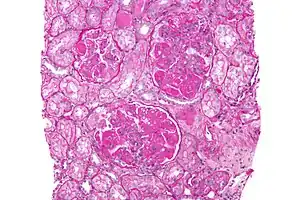

Diffuse Proliferative Lupus Nephritis class IV

Micrograph image of increased mesangial matrix and mesangial hypercellularity due to diffuse proliferative lupus nephritis

A kidney biopsy is the most important diagnostic tool. With a biopsy, the sample will be looked at histologically. With this information, a proper diagnosis can be completed. There are many forms of glomerulonephritis, but under a microscope, DPGN will show increased cell count of polymorphonuclear cells, cellular crescents, and fibrinoid necrosis. A patient with DPGN will have more than 50% of their glomeruli involved.[4][5] If a patient has DPGN, that means they have an active form of glomerulonephritis.[10]